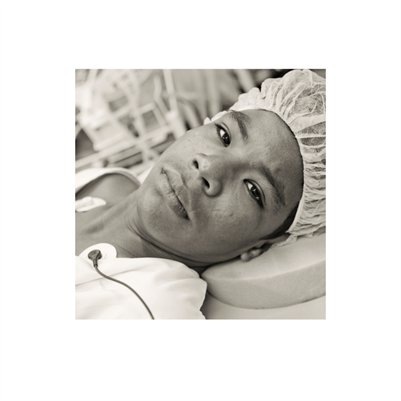

Darkness into the Light. In 2012, The Amazon Project gave eye care to nearly 6000 patients within a 200 kilometer radius of their base in Leticia, Colombia.